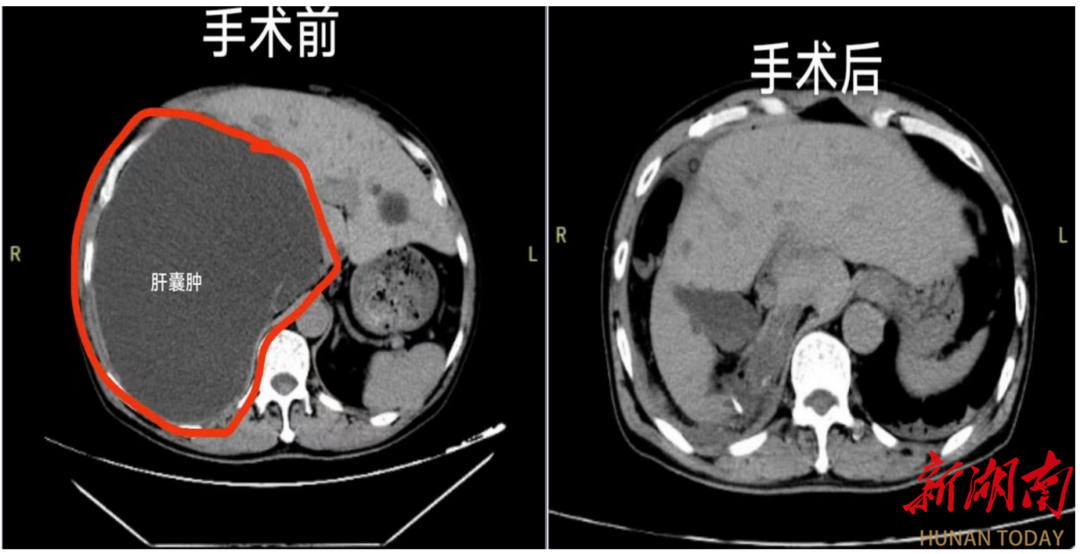

医疗服务提升年∣东安县人民医院肝胆外科成功实施巨大肝囊肿微创手术